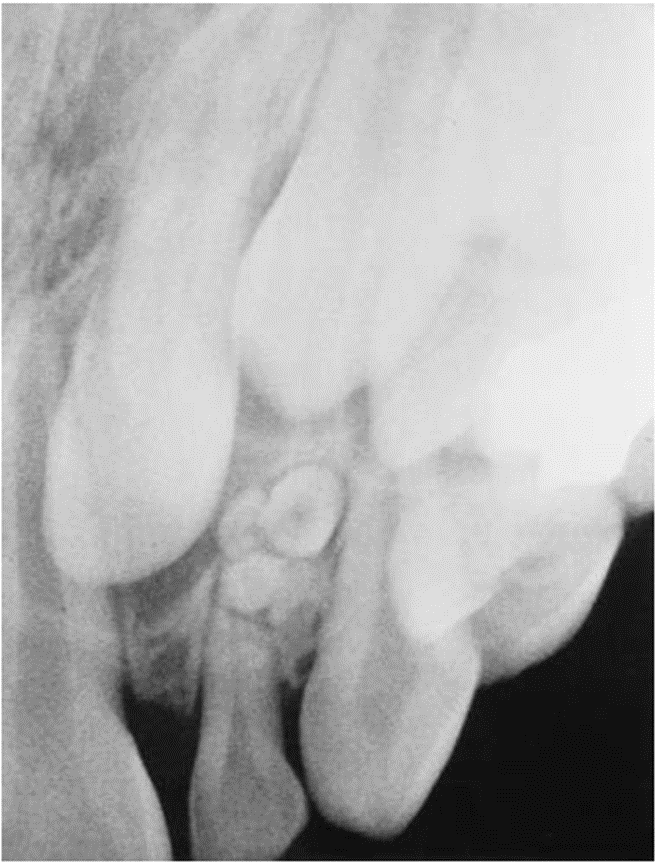

7. (Select ONE OR MORE correct answers)

The 13-year-old healthy boy presents with discomfort from lower right. What is/are the most likely diagnosis/es for tooth 4.5?